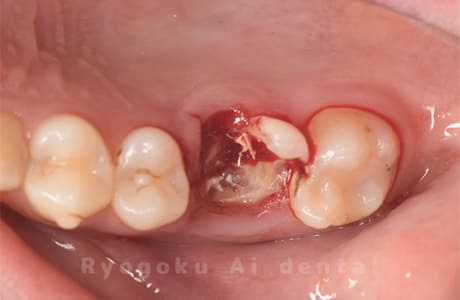

Case21

-

- 原因

- 重度カリエス

- 治療内容

- クラウンレングスニング

- 治療費用

- 44,000円

他院で抜歯と宣告され、当医院を受診された患者様です。クラウンレングスニングを行い、保存を行いました。経過良好です。

<リスク・副作用>

手術後は痛み、腫れ、痺れ、青あざなどの副作用が生じます。痛みは痛み止めを処方しますが、腫れ、青あざは1週間程度生じる場合があります。また、部位によっては神経の走行が複雑で、痺れが残り、長期的にお薬を処方する場合があります。